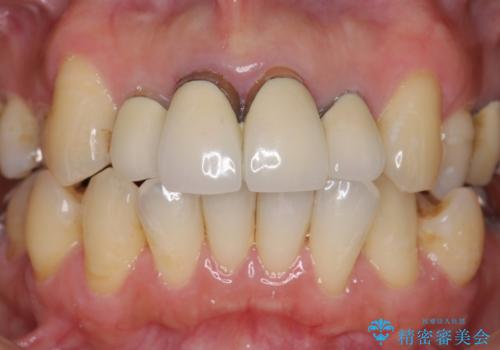

以前に治療した前歯クラウンは月日が経過することで劣化・歯肉の位置変化を引き起こし審美障害を引き起こしています。

劣化したクラウンを除去し、再発した虫歯を徹底的に除去したのち根管治療・ファイバーコア築盛を行いジルコニアクラウン製作へと移ります。